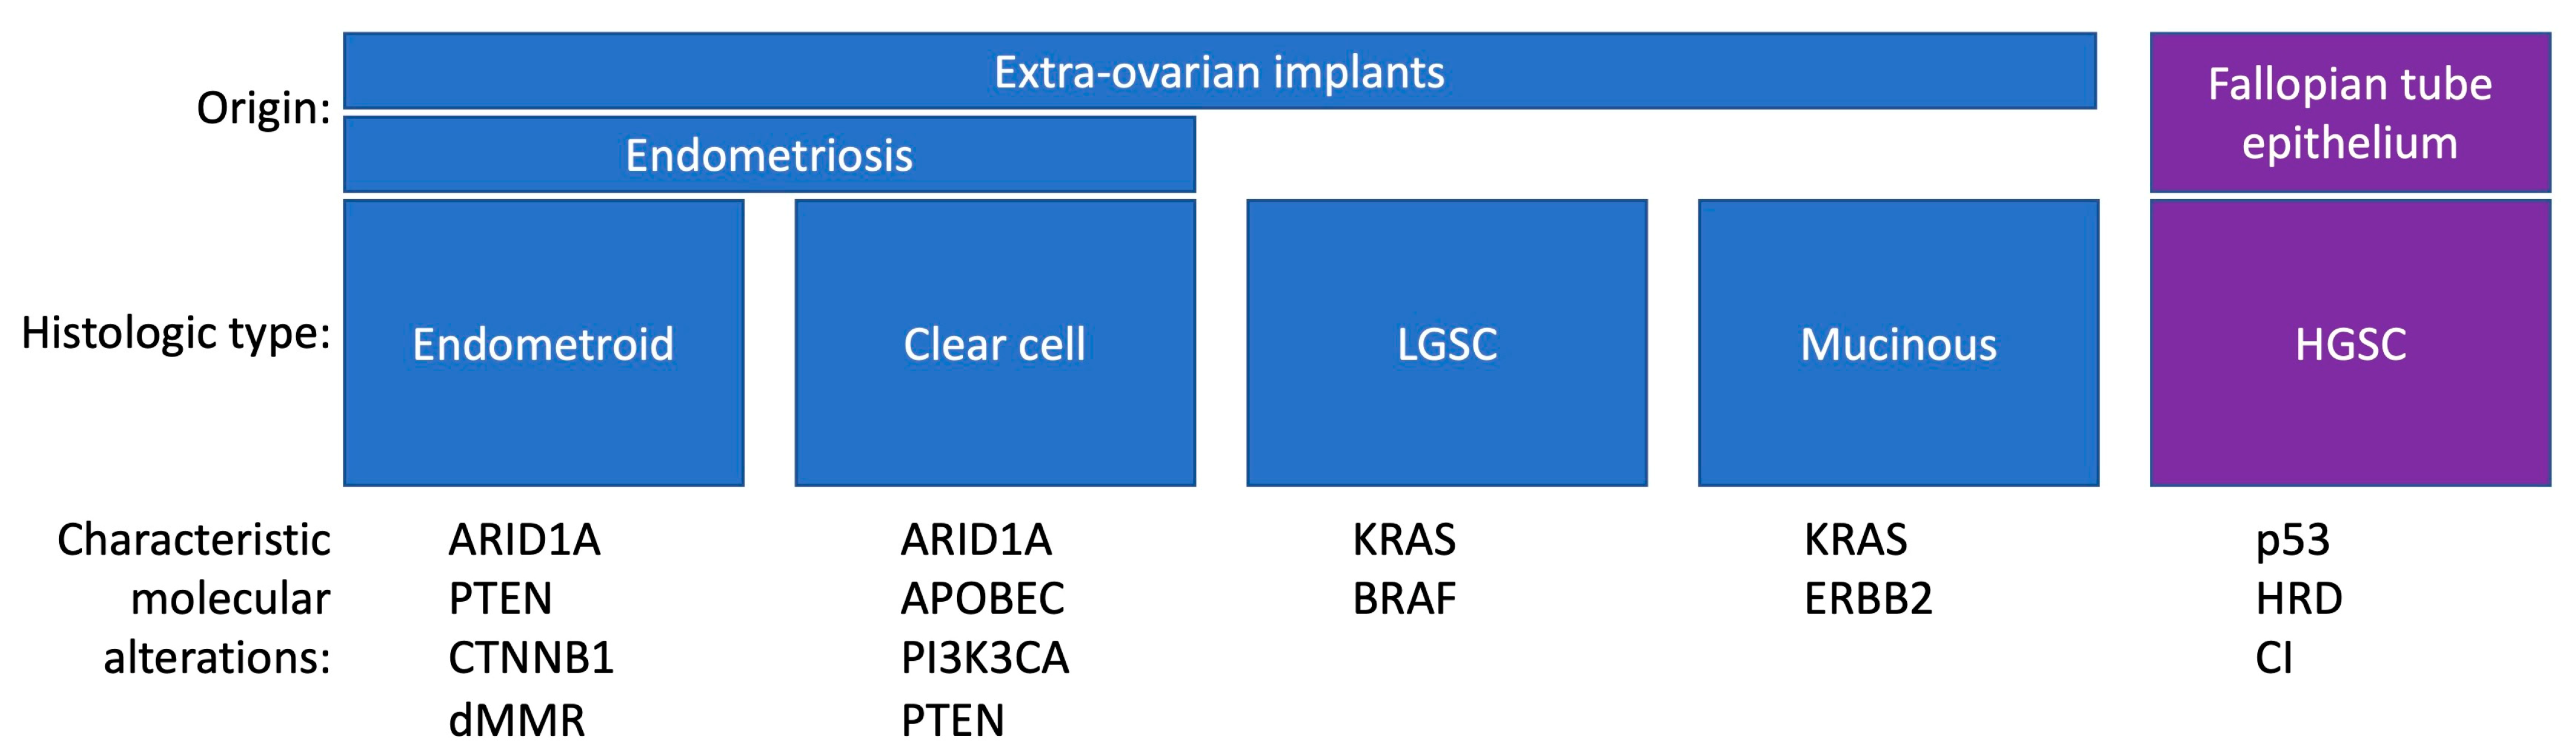

2. Pathogenesis of Ovarian Cancer

3.2. Histology and Pathogenesis of Endometriosis-Associated Ovarian Cancer

- Prat, J. Ovarian carcinomas: Five distinct diseases with different origins, genetic alterations, and clinicopathological features. Virchows Arch. 2012, 460, 237–249. [Google Scholar] [CrossRef] [PubMed]

- Shih, I.-M.; Kurman, R.J. Ovarian tumorigenesis: A proposed model based on morphological and molecular genetic analysis. Am. J. Pathol. 2004, 164, 1511–1518. [Google Scholar] [CrossRef] [PubMed]